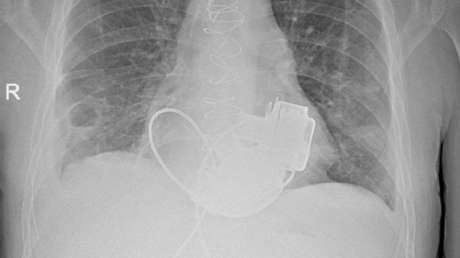

La operación duró unas 12 horas. En el proceso participaron especialistas de diferentes ámbitos, siendo la microcirugía la fase más difícil, ya que implica conectar con precisión nervios, vasos, músculos y tendones del injerto y del paciente.